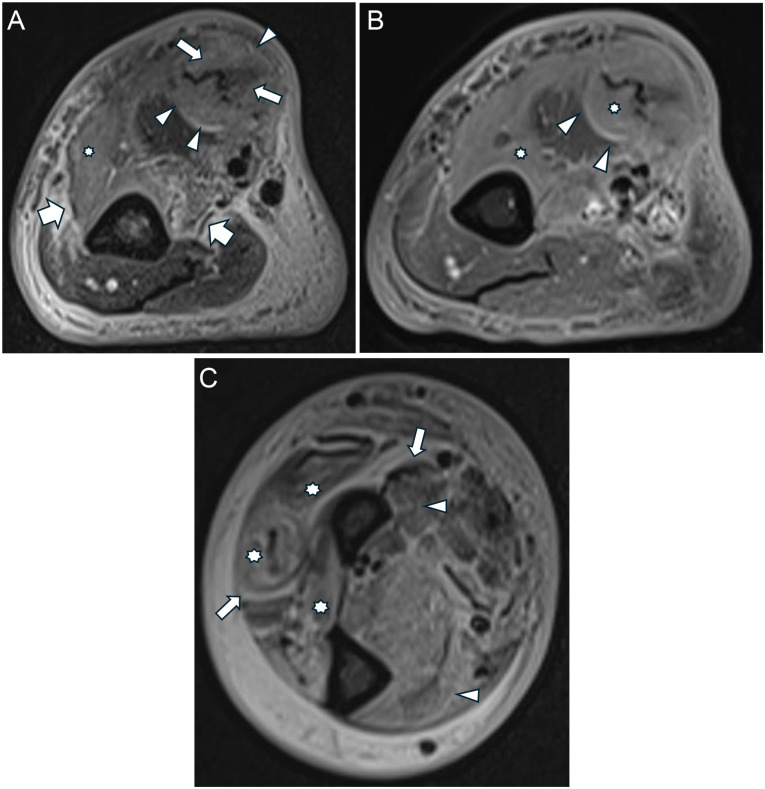

结核性坏死性筋膜炎(NF)是一种极其罕见的疾病,特别是在因自身免疫性疾病(如类风湿关节炎)接受免疫抑制治疗的患者中。本病例描述了一名69岁男性,有阿达木单抗治疗的类风湿关节炎病史,表现为右上肢剧烈疼痛、肿胀和发红。尽管最初治疗推定为细菌性NF,但组织学检查和结核(TB)聚合酶链反应(PCR)证实结核性筋膜炎。患者表现出呼吸道症状,影像学显示提示肺结核的空洞性病变,痰液PCR也证实了这一点。不幸的是,病人在治疗期间死于急性心肌梗死。本病例强调了在鉴别诊断坏死性筋膜炎时考虑结核病的重要性,特别是在免疫功能低下的个体中,以确保及时和适当的治疗。

Tuberculous necrotizing fasciitis (NF) is an exceedingly rare condition, particularly in patients undergoing immunosuppressive therapy for autoimmune diseases such as rheumatoid arthritis. This case describes a 69-year-old male with a history of rheumatoid arthritis treated with adalimumab, who presented with severe pain, swelling, and redness in the right upper limb. Despite initial treatment for presumed bacterial NF, histological examination and tuberculosis (TB) polymerase chain reaction (PCR) confirmed tuberculous fasciitis. The patient exhibited respiratory symptoms, and imaging revealed a cavitary lesion suggestive of pulmonary tuberculosis, which was also confirmed by sputum PCR. Unfortunately, the patient succumbed to an acute myocardial infarction during treatment. This case highlights the importance of considering TB in the differential diagnosis of necrotizing fasciitis, particularly in immunocompromised individuals, to ensure timely and appropriate management.